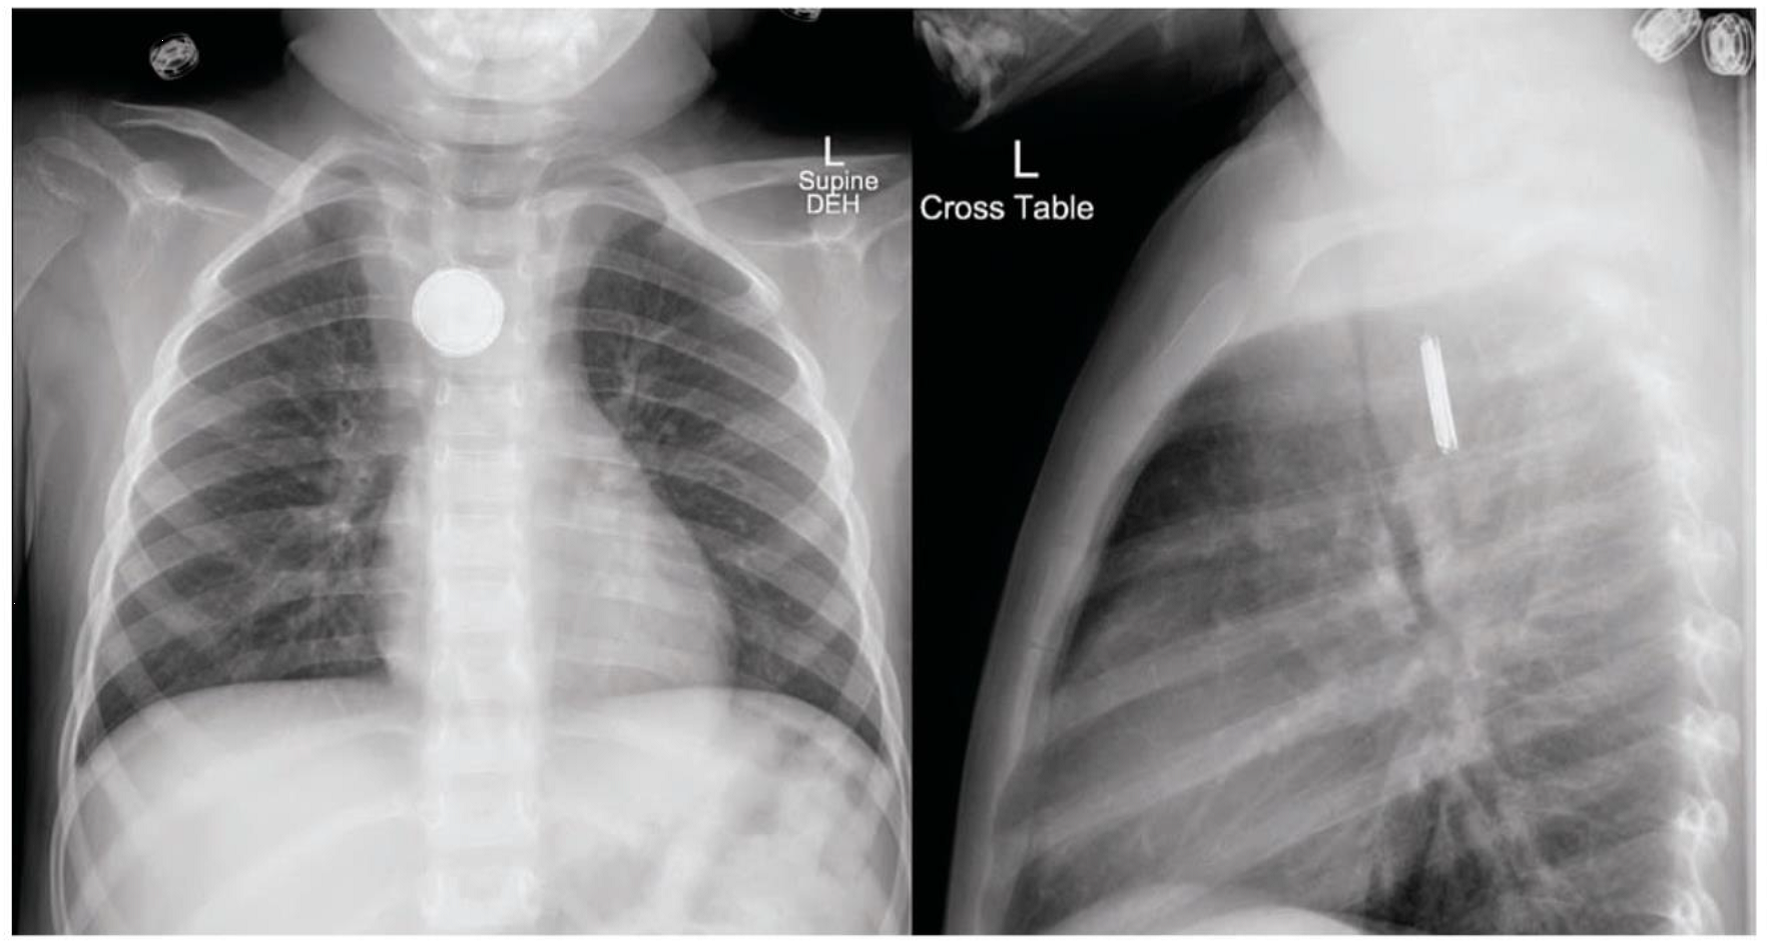

A 4-year-old girl is brought to the ED by parents with the complaint of chest pain and abnormal behavior, consisting of not talking and refusing PO intake. On exam, vital signs: BP 105/75 HR 122/min, RR 26/min, Pulse ox 98%. The child was restless, irritable, and held her neck in extension. Neck, chest, and abdomen x-rays were obtained.

Fig 1: Antero-posterior and lateral chest x-rays showing a radiopaque foreign body in the esophagus.

- Patients suspected of a button battery ingestion should be kept NPO and x-rays should be obtained of the neck, chest (AP and lateral), and abdomen as soon as possible. Infants can have a whole body x-ray, known colloquially as a “baby-gram.”